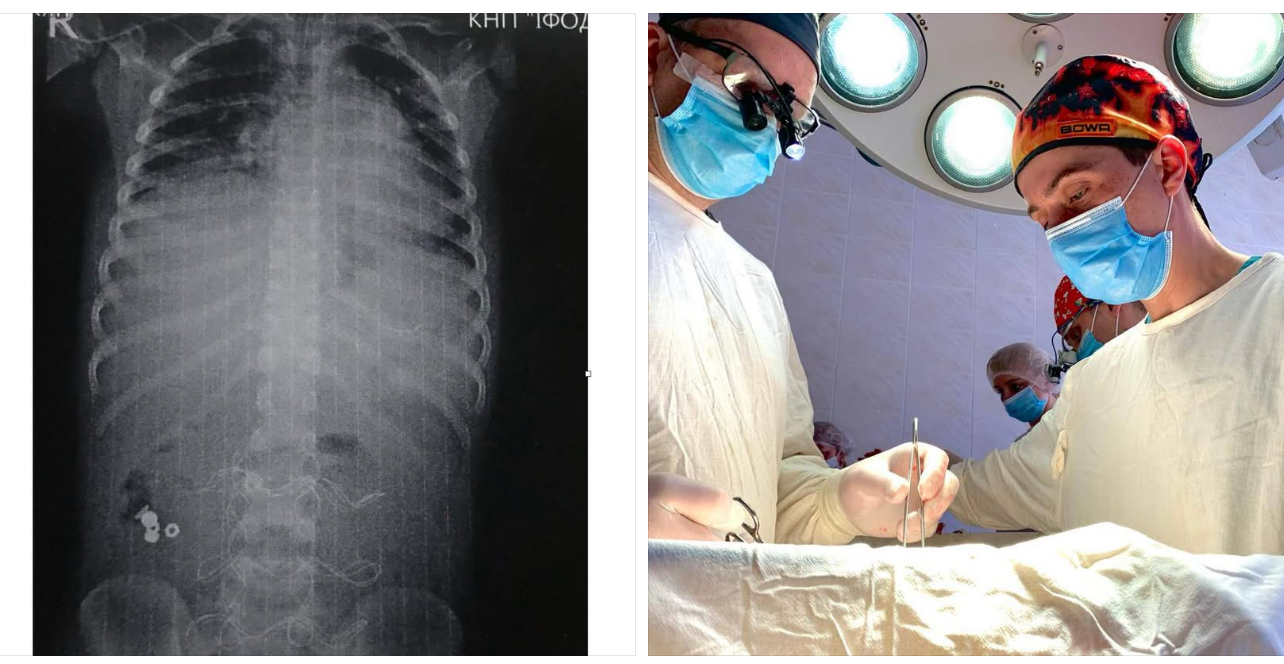

В Івано-Франківській обласній дитячій клінічній лікарні лікарям вдалося врятувати життя 7-річного хлопчика, який потрапив до медзакладу у вкрай тяжкому стані.

Як повідомив генеральний директор ОДКЛ Тарас Мельник, дитину доправили з ознаками інфекційно-токсичного шоку та клінікою розлитого перитоніту.

«Поділюся з вами медично складною історією з, на щастя, хорошим кінцем. До нас в ОДКЛ привезли 7-річного хлопчика у вкрай тяжкому стані інфекційно-токсичного шоку з клінікою розлитого перитоніту. Як виявилось, усе сталося через батарейку, яку дитина проковтнула, що спричинило перфорацію тонкого кишківника», — розповів Тарас Мельник.

Передопераційна підготовка тривала 12 годин. Загалом медики провели три оперативні втручання. Лише на 20-ту добу після госпіталізації хлопчика виписали зі стаціонару у задовільному стані.